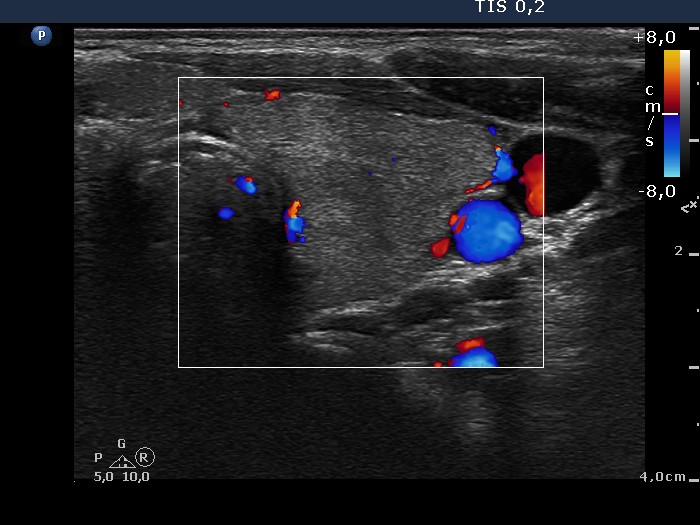

Follow-up investigation 40 months after first visit (ultrasonographic picture 6)

Patient on daily 5 mg methimazole therapy in hypothyroid state

Left lobe, transverse scan, color Doppler mode. The vascularization is practically absent within the thyroid parenchyma.